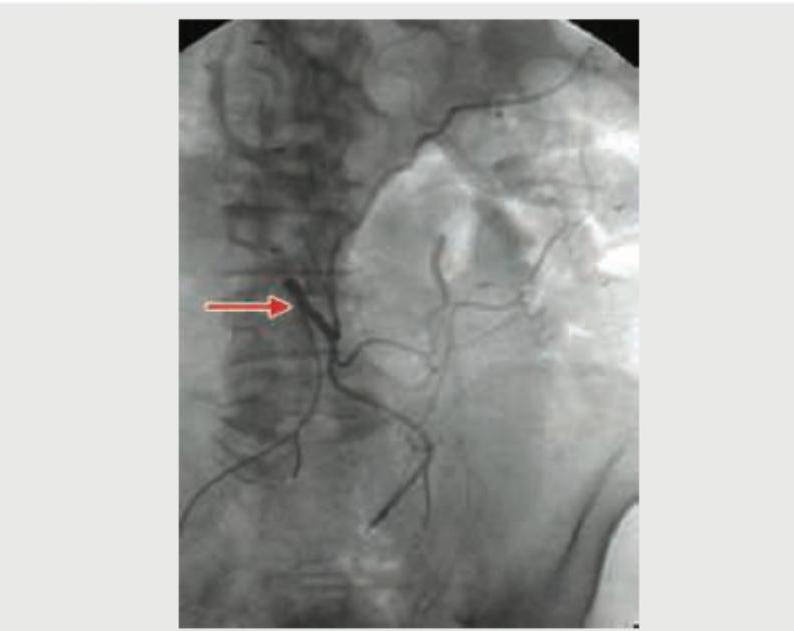

The Gut blood vessel marked (Red arrow) in the angiogram is: (Recent NEET Pattern 2018-19)

Explanation: ***Superior mesenteric artery*** - The image shows an **abdominal angiogram** with a vessel arising from the anterior aspect of the aorta and branching extensively, consistent with the **superior mesenteric artery (SMA)**. - The SMA typically supplies the **midgut structures**, which include the duodenum (distal to the major duodenal papilla), jejunum, ileum, cecum, ascending colon, and the proximal two-thirds of the transverse colon. *Inferior mesenteric artery* - The **inferior mesenteric artery (IMA)** originates lower down the aorta, usually at the level of L3, and supplies the hindgut (distal one-third of the transverse colon, descending colon, sigmoid colon, and rectum). - The branching pattern and location in the angiogram do not match the expected origin and distribution of the IMA. *Splenic artery* - The **splenic artery** is a branch of the celiac trunk, which arises higher than the vessel shown and typically courses towards the left to supply the spleen, stomach, and pancreas. - Its branching pattern and location are distinctly different from the vessel highlighted in the image, which is clearly supplying mesenteric structures. *Gastroepiploic artery* - The **gastroepiploic arteries** (right and left) are branches primarily supplying the greater curvature of the stomach and the greater omentum. - These arteries are much smaller and are situated along the stomach, not originating directly from the aorta in this manner or having such a widespread mesenteric distribution.